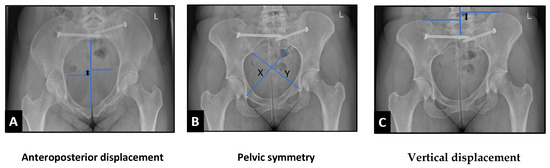

Background/Objectives: Uroflowmetry is done in the surveillance period after End-to-end Anastomotic Urethroplasty for pelvic fracture urethral injury. But is maximum flow rate a reliable surrogate for urethral calibre in these cases? The above question laid the foundation of the study. The aim of the study was: “Is uroflowmetry alone sufficient to predict a successful outcome following urethroplasty after pelvic fracture urethral injury (PFUI)?” Methods: We conducted a prospective masked study of all patients undergoing end-to-end anastomosis (EEA) urethroplasty for PFUI from January 2017 to September 2022. The first follow-up was 4 weeks after surgery, micturating cystourethrogram (MCU) was done after urethral catheter removal and at the same time, uroflowmetry was also done. The second follow-up was 6 months after surgery, when uroflowmetry was repeated, and urethroscopy was performed. The urologist performing urethroscopy was blinded to the uroflowmetry results. Results: In total, 26 patients were included in the study. After 6 months, 1 patient had poor flow (maximum flow rate [Q max] < 10 mL/s), 7 patients had flow with Q max 10–15 mL/s, and 18 patients had normal flow (Q max > 15 mL/s). On urethroscopy, all patients had a normal and easily passable urethra. The International Prostate Symptom Score (IPSS) and quality of life (QoL) scores showed a positive correlation. The urologist performing urethroscopy and the investigator recording uroflowmetry reached different conclusions. Conclusions: A reduced peak on uroflowmetry after EEA urethroplasty in PFUI does not always indicate surgical failure. Urethroscopy enables direct visualisation of the anastomotic site and provides more detailed information than uroflowmetry. The IPSS score and quality of life are more important than Q max alone. Full article